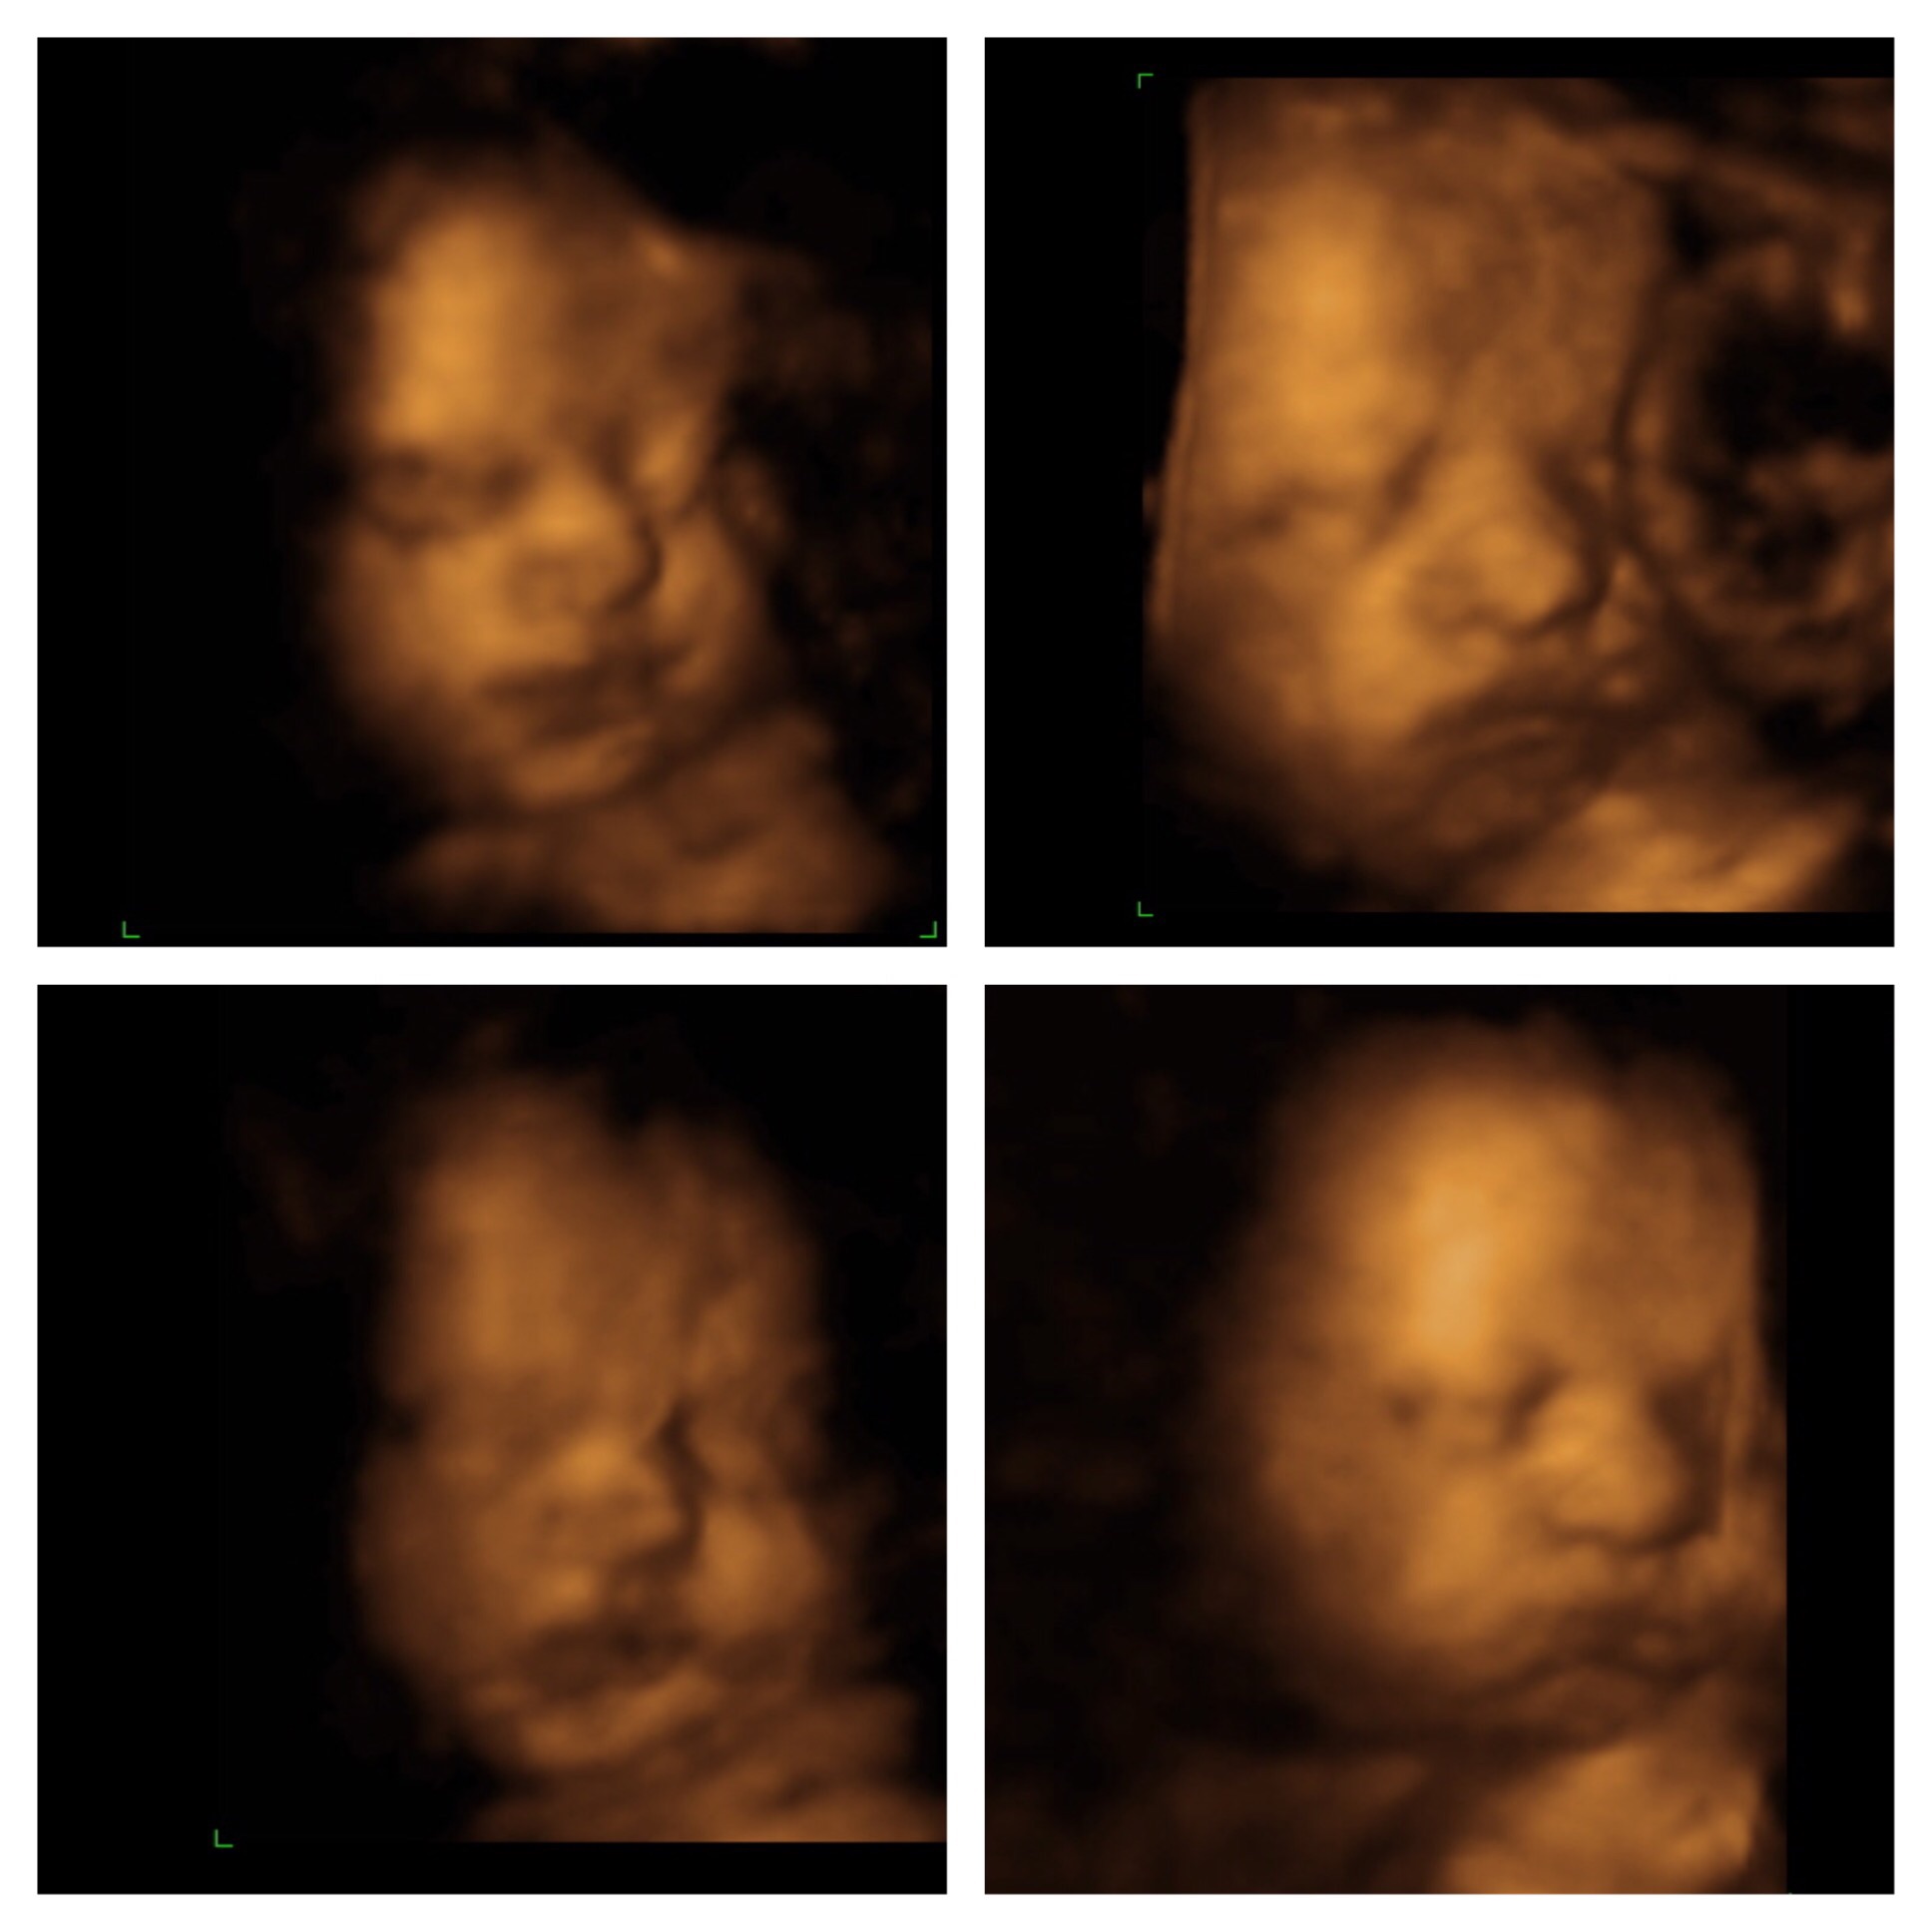

We went for our 4D Ultrasound this weekend and I was so excited to finally get a glimpse at my little one. I am low-risk and my insurance only covers 2 ultrasounds so I haven't seen my little one since 20 weeks (and I'm 30 weeks now). So we loaded up and drove a little ways (as there are not an elective Ultrasound places near us). The whole way down to the place my belly is moving and grooving and turning and as soon as we get there...nothing. He had his hands and feet in front of his face. We did see that we will definitely be having a BOY!!! The tech tried jiggling my belly, filling my bladder, emptying my bladder, I drank ice cold water, juice and ate some candy...he slept through the whole thing. We do get to go back this weekend to try again but I was a little disappointed. Luckily he will be here sooner than later.